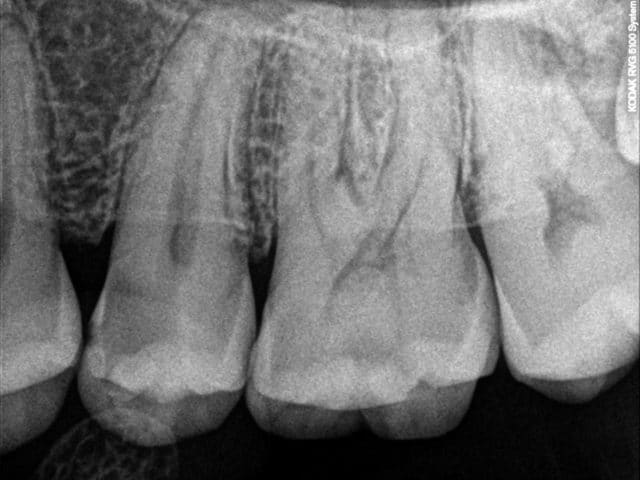

barbabapat

09/10/2015 à 14h31

Enfin, combien de temps va on continuer avec ce genre de conneries.

Patient qui ne consulte pas pendant 15 ans, pas de douleur spontanées.

Pourquoi, rien ne l'as invité à faire une surveillance régulière de ses dents.

Pourquoi, la réalisation de deux soins Sur 25 et 26 devrait se réaliser à perte.

Comment se fait il que les traitements les plus mutilant seraient à privilégier du point de vue de la mutuelle pour justifier l’utilité de jeter l'agent par les fenêtres et pour moi en temps que praticien si je réfléchi en terme de bénéfice.